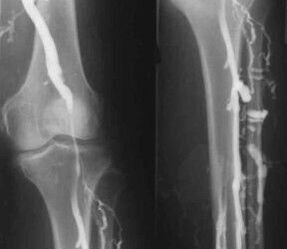

Diagnostiko instrumental-metodorik ohikoena hanketako beno-hodien ultrasoinuen azterketa erabiltzea da. Teknika honek sistema baskularra ikusteko eta prozesu patologikoaren aurrerapen-maila identifikatzea ahalbidetzen du.

- Flebografia.